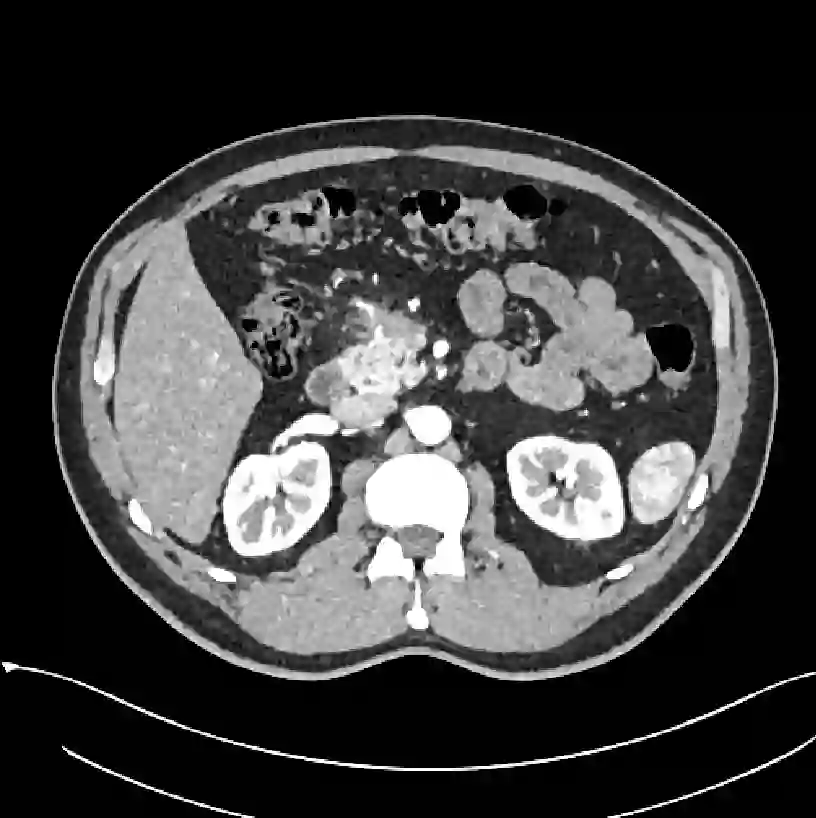

Early tumor detection save lives. Each year, more than 300 million computed tomography (CT) scans are performed worldwide, offering a vast opportunity for effective cancer screening. However, detecting small or early-stage tumors on these CT scans remains challenging, even for experts. Artificial intelligence (AI) models can assist by highlighting suspicious regions, but training such models typically requires extensive tumor masks--detailed, voxel-wise outlines of tumors manually drawn by radiologists. Drawing these masks is costly, requiring years of effort and millions of dollars. In contrast, nearly every CT scan in clinical practice is already accompanied by medical reports describing the tumor's size, number, appearance, and sometimes, pathology results--information that is rich, abundant, and often underutilized for AI training. We introduce R-Super, which trains AI to segment tumors that match their descriptions in medical reports. This approach scales AI training with large collections of readily available medical reports, substantially reducing the need for manually drawn tumor masks. When trained on 101,654 reports, AI models achieved performance comparable to those trained on 723 masks. Combining reports and masks further improved sensitivity by +13% and specificity by +8%, surpassing radiologists in detecting five of the seven tumor types. Notably, R-Super enabled segmentation of tumors in the spleen, gallbladder, prostate, bladder, uterus, and esophagus, for which no public masks or AI models previously existed. This study challenges the long-held belief that large-scale, labor-intensive tumor mask creation is indispensable, establishing a scalable and accessible path toward early detection across diverse tumor types. We plan to release our trained models, code, and dataset at https://github.com/MrGiovanni/R-Super